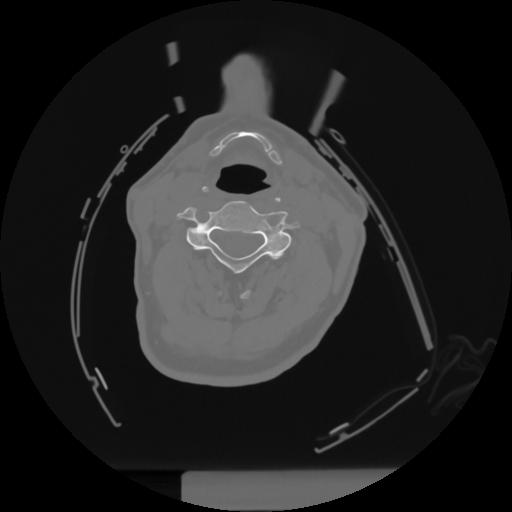

12 P.BLANDAS,,Vol,0.5,P.BLANDAS,,